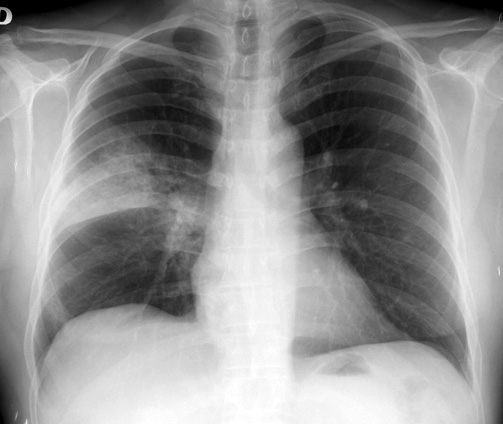

Efectividad de la vacuna antineumocóccica 23-valente en mayores de 65 años

24 enero 2017

La vacuna redujo en un 33% las neumonías por serotipos incluidos en la vacuna, y en un 27% el total de neumonías por neumococo en esta población. Lancet Infectious Diseases, 23 de enero de 2017